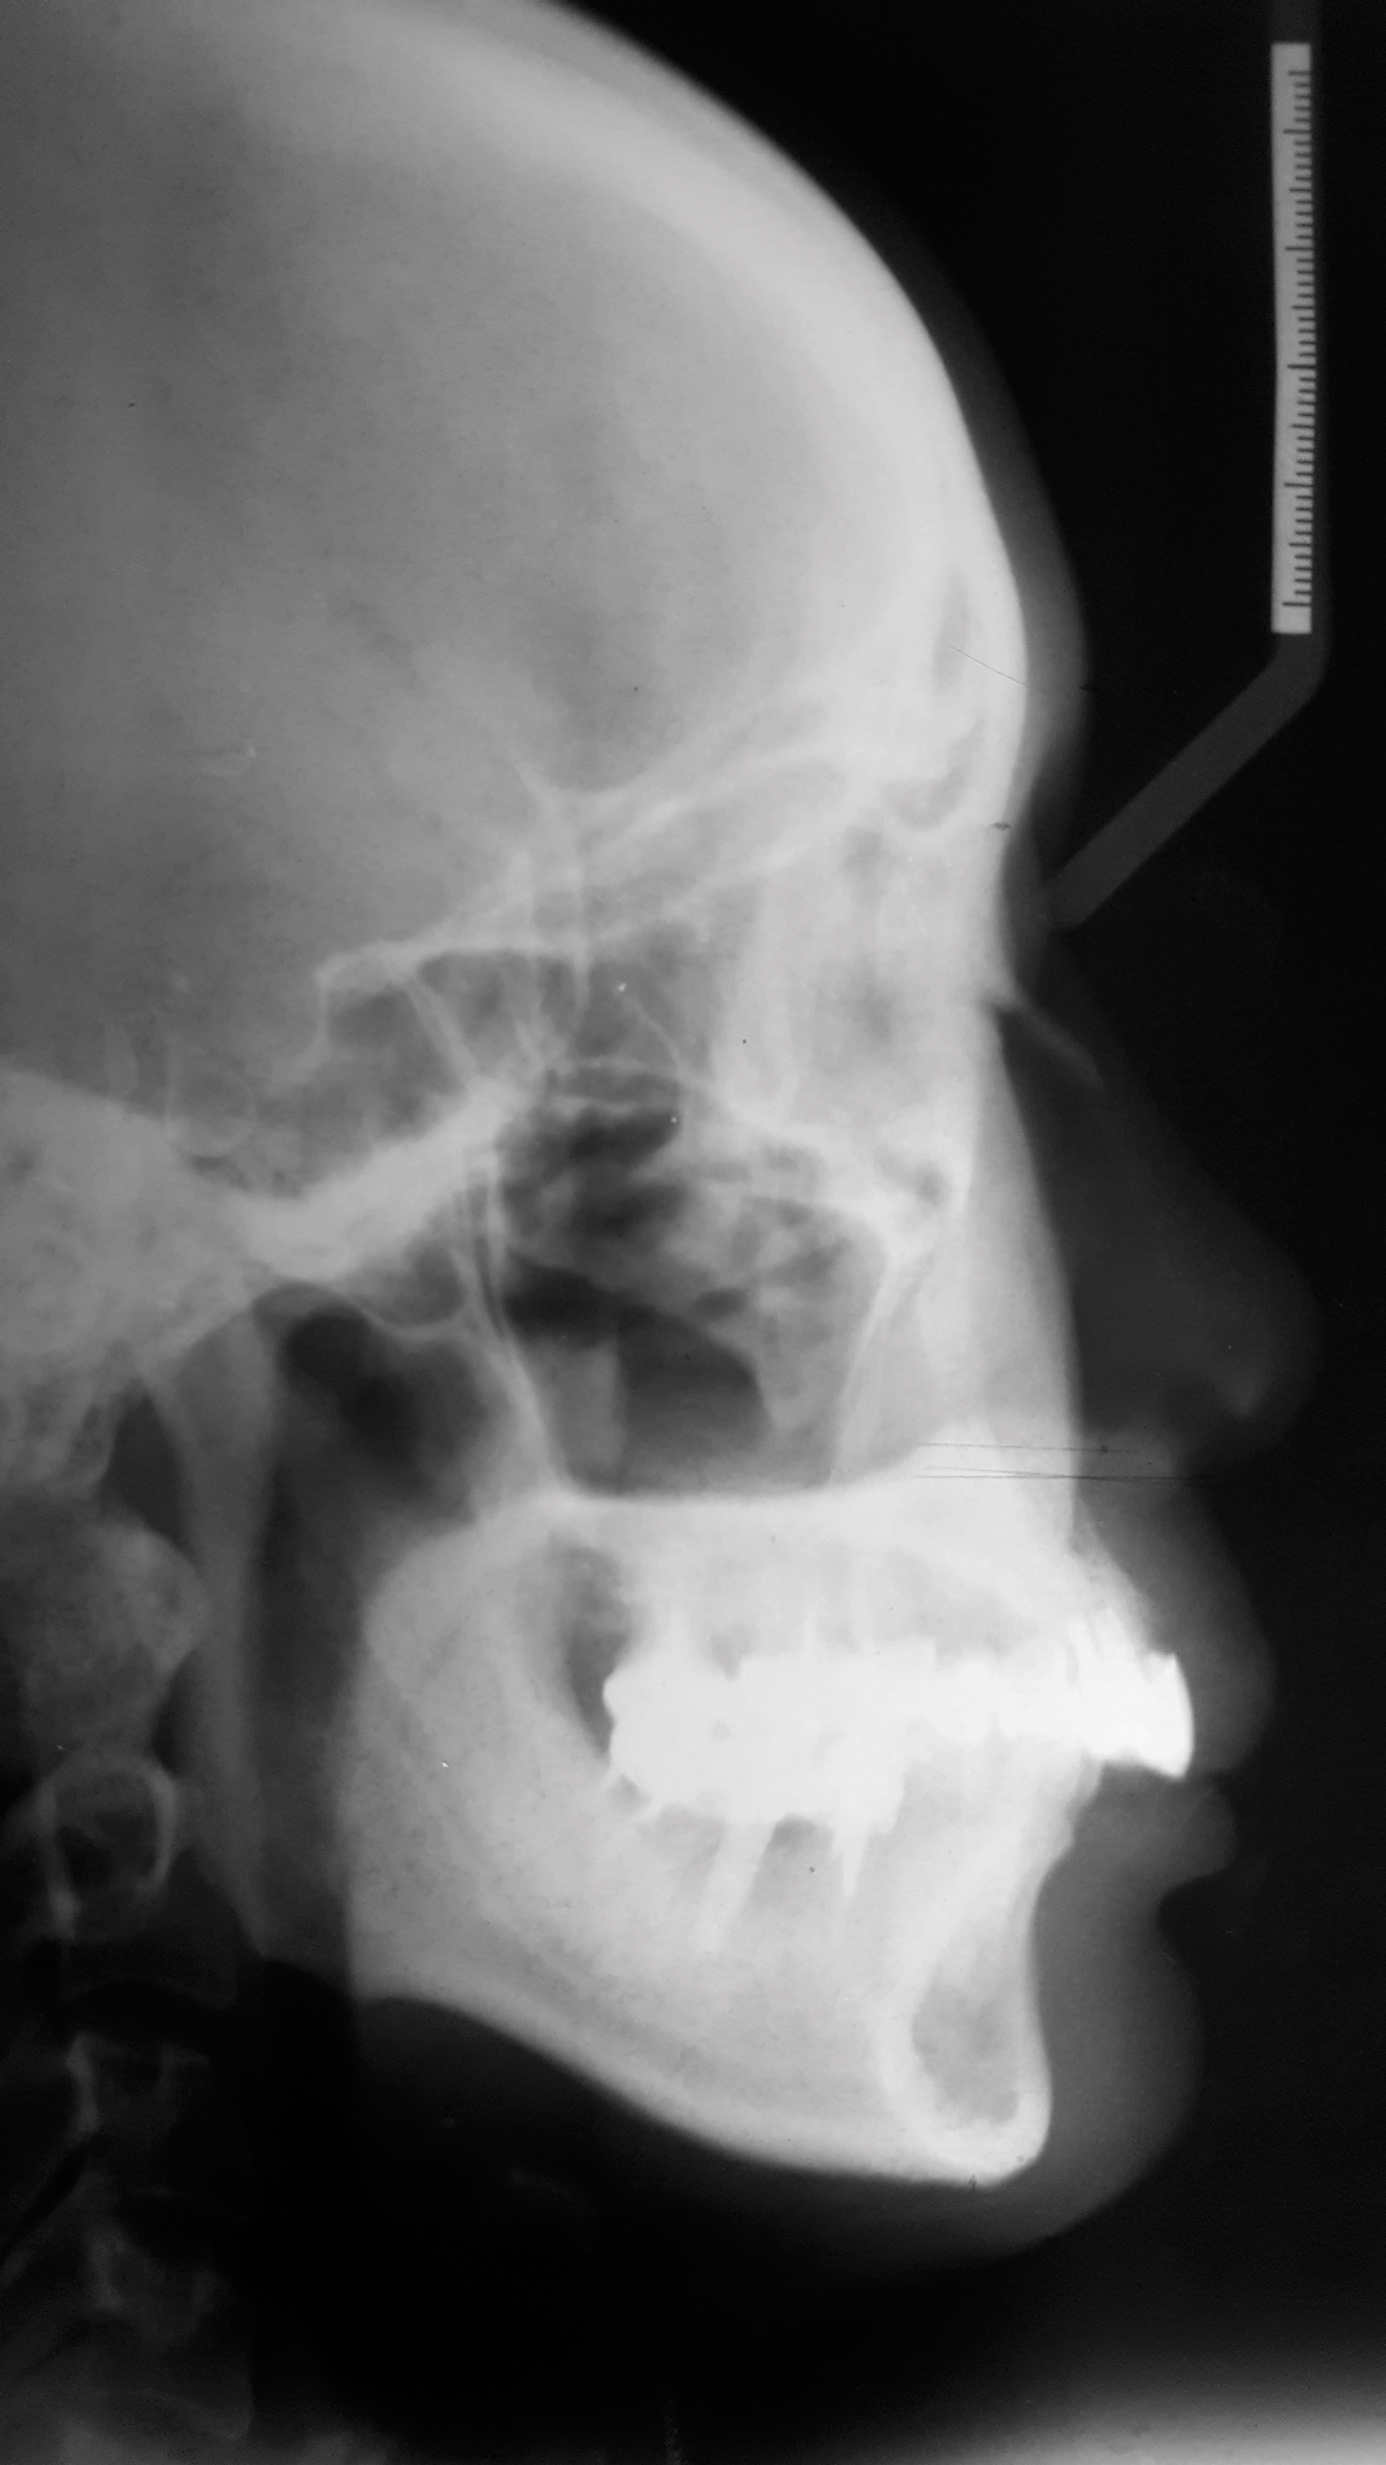

From radiographic examination, tooth No. 18 was found to have a poor prognosis due to furcation bone loss. The cephalometric x-ray showed a skeletal class II relationship, a reduced mandibular plane angle, flared upper incisors, a deep bite, and significant overjet (Figure 6). The panoramic radiograph confirmed many restorations and that No. 19 was a dental implant (Figure 7). There were no symptoms of temporomandibular joint disorder.

Fig 6. Cephalometric film before treatment.

Figure 6